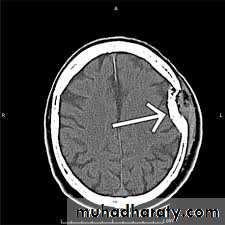

Slide 121- What is the finding in this CT?2- By what chart you follow this patient?